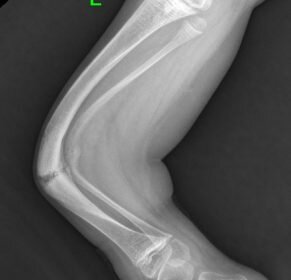

Несовершенный остеогенез – тяжелое наследственное заболевание, основным проявлением которого является нарушение структуры и прочности костей, приводящее к частым переломам костей.

Дети, страдающие этим заболеванием ограничены в своих возможностях в связи с риском возникновения перелома без адекватной травмы, а также из –за деформаций конечностей.

Без адекватного лечения заболевание нередко приковывает пациентов к постели, изолирует от общества, препятствует нормальному психомоторному развитию, интеграции в детских коллективах и, в дальнем, в социуме. Часто даже невозможно осуществлять за ними необходимый уход из-за постоянного риска возникновения патологических переломов на фоне врожденного и вторичного гипокинетического остеопороза.

Многие дети с несовершенным остеогенезом, имеющие деформации конечностей, нуждаются в хирургическом лечении – выполнении корригирующих остеотомий с фиксацией металлическими конструкциями, которые предохраняют кость от повторных переломов. До недавнего времени для этого были доступны металлоконструкции, используемые в других областях травматологии и ортопедии. Они имеют постоянную длину и не удлиняются вместе с ростом кости. Это приводило к переломам выше и ниже металлоконструкции, что требовало многочисленных повторных операций